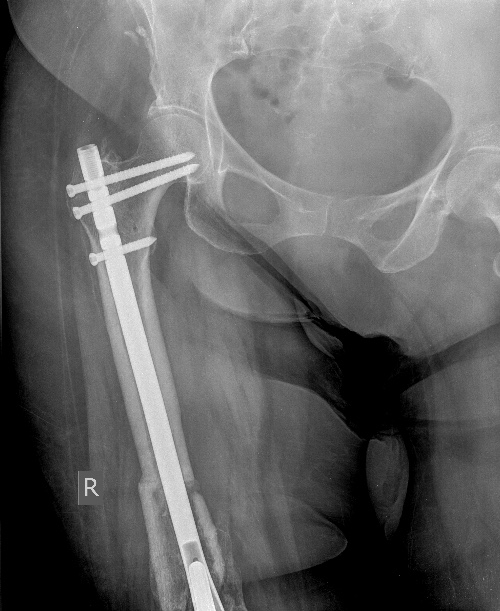

Здравствуйте, уважаемые коллеги. Нужен Ваш совет.15-летний подросток. В возрасте 14 лет выявлена остеогенная саркома большеберцовой кости, после предварительного курса ПХТ оперирован в феврале 2016 г. в столичной клинике, выполнена резекция костей голени с опухолью, эндопротезирование коленного сустава. 3 дня назад - травма - подвернул ногу, упал. Имеем перелом бедра на уровне проксимального штифта протеза. Учитывая, что с эндопротезами мы дело в детском отделении не имеем, опыта лечения подобных больных нет. Связывались с отделением, где ребёнка оперировали, там посоветовали коксит на 2-3 месяца.Но... 1. Подобный перелом удержать в коксите - более чем непростая задача, да и понадобится, наверное, не 2-3 месяца. 2. Хочется всё-таки мобилизовать ребёнка, он и так уже 2 с лишним года лечился от более чем серьёзной болезни, ходил на костылях. В связи с чем прошу совета, как быть. Оставить всё-таки в коксите? Оперировать? Если да, то чем? В наличии - аппарат Илизарова, стержневые аппараты, пластины без УС, детские блокированные гвозди Остеомед.Собственные мысли - купим длинную пластину с угловой стабильностью, постараемся провести шурупы мимо ножки эндопротеза. Либо комбинированный спице-стержневой аппарат опять-таки, спицы вне ножки протеза.Хотелось бы узнать мнения более опытных коллег.Заранее спасибо.

Оптимальное решение - закрытый остеосинтез интерамедуллярным стержнем с удлинением ножки эндопротеза. Пример в приложении. Делает такие стержни предприятие ЦИТО.

Все прошло по плану. Длину восстановили дистрактором. Пришлось сделать небольшую чрескожную остеотомию, чтобы устранить смещение по ширине.